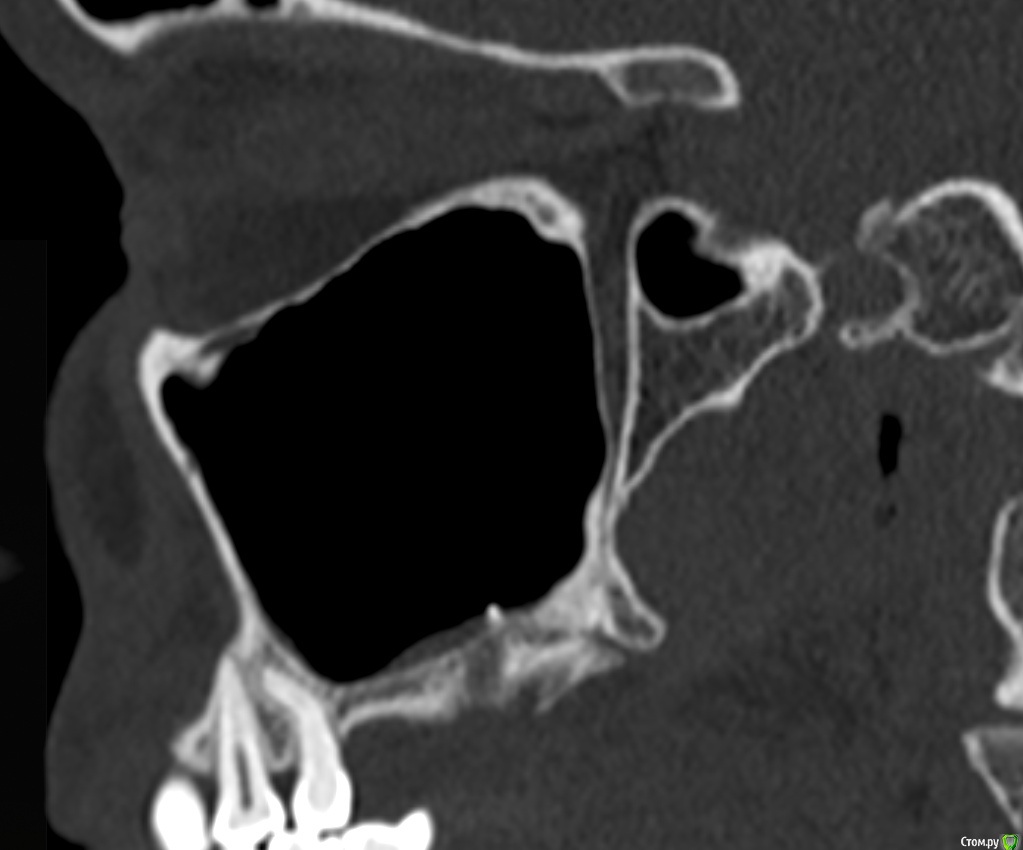

Фрагмент кости в гайморовой пазухе. Нет гноя. Причина болей?

Здравствуйте. На протяжении 5 месяцев беспокоит боль в области между левой пазухой и челюстью. Боль острая, ноющая как при боли в зубе. Верхняя 7а слева (депульпированная) удалена месяц назад, но боль только усилилась. Со временем стали болеть и все суставы в теле, в особенности руки и ноги. Выполнять простые движение стало очень больно. На КТ видны инородные фрагменты и нарушение целостности нижней стенки пазухи, но в Спб никто их не захотел удалять инородные фрагменты из-за того, что причина боли по мнению врачей не в этом. В результате боль только усиливается. Причину боли при моей картине КТ никто установить не может. Обращалась почти во все клиники. Несколько неврологов патологию лицевого нерва исключили. Все это время держится температура 37-37,5. Ощущение сильного воспалительного процесса, боль немного стихает на приеме антибиотиков, но ненадолго, примерно на неделю - две. Обычные обезболивающие совершенно не помогают. Жевать пищу очень больно, сильно рот не открыть. Слабость и нет аппетита. Может ли так организм реагировать на инородный фрагмент кости в пазухе или дело в другом? Возможно ли что есть какие-то нарушения (переломы, трещины и пр) кости, которые требуют хирургического вмешательства?Вопрос возник по той причине, что при промывании пазухи есть ощущение проникания жидкости куда-то за пределы слизистой и после промывания состояние заметно ухудшается. Если кто-то может помочь советом буду очень признательна. Есть несколько КТ 3д. https://yadi.sk/d/PX30GoO1Cn5m_w -  от 13.06.2020 (примерно сразу после появления болевого синдрома), https://yadi.sk/d/bm7FD9SYVw2-Gw- сразу перед удалением зуба,  https://yadi.sk/d/fbaOTQT2-ya4xQ - КТ пазух от 21.11.2020 (то что есть на сегодня).